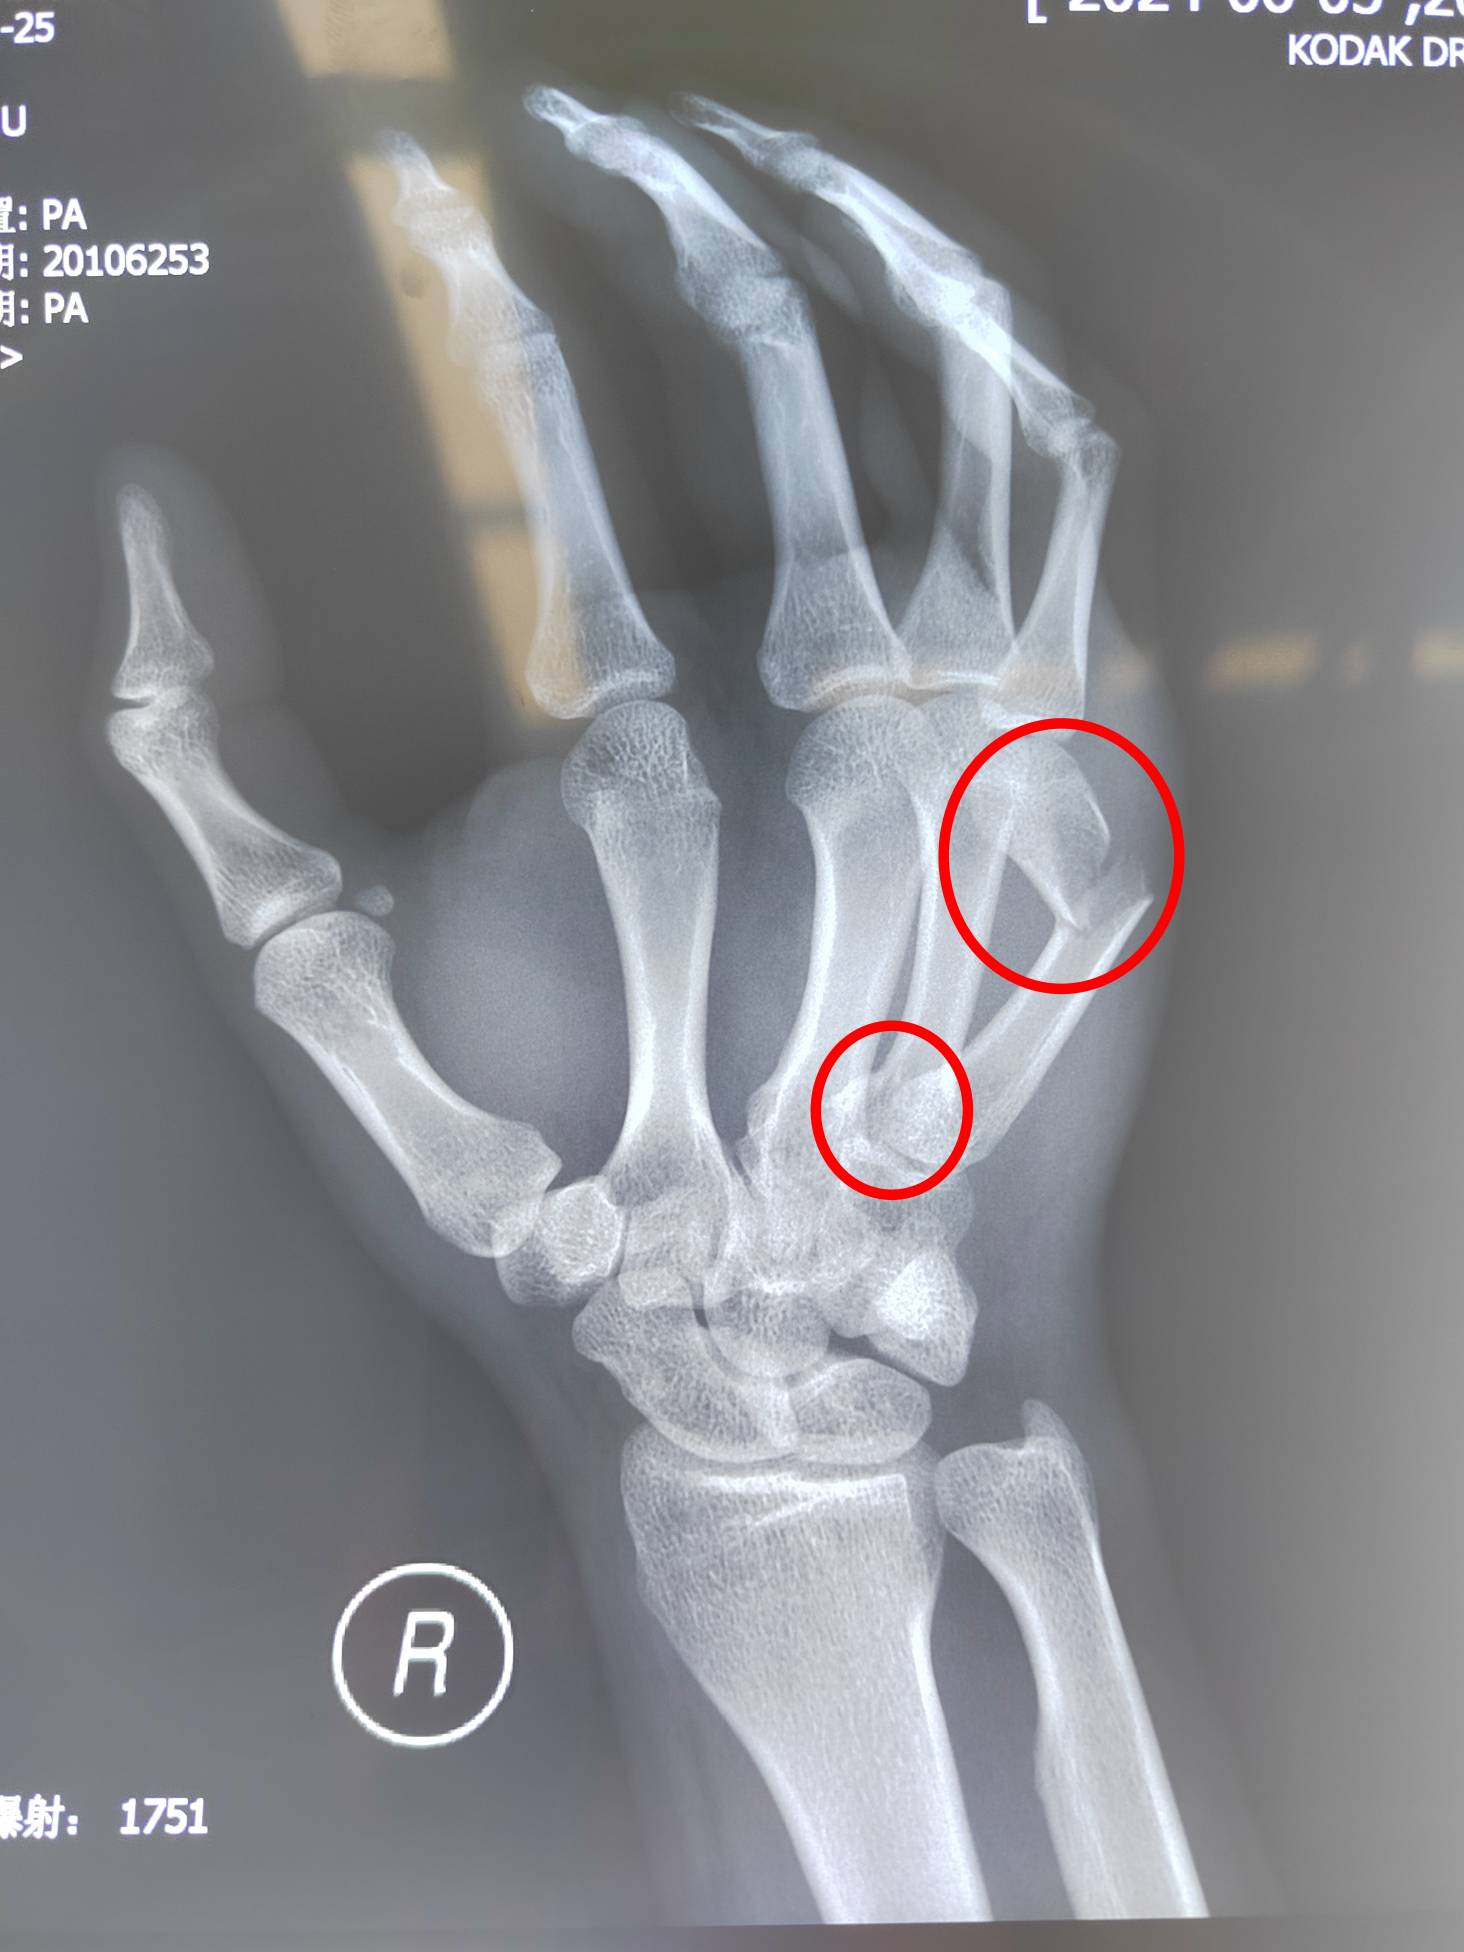

对于每一位高三考生来说,高考是当前最为重要的事情,今年20岁的小马,是孟津区的一名高三考生,2024年6月4日晚上不慎摔伤,导致右手疼痛难忍。到附近医院检查后发现“右手第5掌骨颈骨折,右手第4掌骨基底部骨折”。右手对于一个即将参加高考的高三学生来说,重要性不言而喻,右手骨折后还能不能顺利参加高考成了一个未知数。这场突如其来的意外,使一家人笼罩在阴影之中,焦虑万分。有医生建议放弃考试,先治疗骨折,也有医生建议先忍痛参加考试,考完后再治疗骨折,如何抉择成为摆在家长面前的一道难题。

术前影像检查